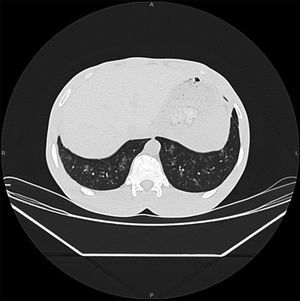

Paciente varón de 29 años natural de Senegal, residente en España desde hace 7 años, no ha regresado a su país. Trabaja en invernaderos. No refiere alergias medicamentosas ni enfermedades previas. Consulta a urgencias hospitalarias por cuadro de tos con expectoración purulenta de 2 meses de evolución acompañados de disnea a moderados esfuerzos y dolor punzante retroesternal y sensación distérmica en el último mes. En la exploración física presenta crepitantes y sibilantes teleinspiratorios en ambos campos medios pulmonares. En la analítica solo destaca una eosinofilia moderada (1.640 eosinófilos/μl, 21,9% de 7.490μl leucocitos), hemoglobina 16,6g/dl, plaquetas 287.000μl; siendo la bioquímica, el perfil hepático y el renal, normales. La radiografía de tórax no mostró alteraciones. Se indica tratamiento con antibióticos, broncodilatadores y corticoides inhalados. Se remite a la consulta de Medicina Tropical donde se realiza analítica que confirma la eosinofilia. Las serologías de lúes, VHC y VIH fueron negativas, y la de VHB: AgHBs+, AcHBc+, AcHBs−. IgE 1.523 UI/ml. Mantoux 8mm. El estudio parasitológico inicial mostró parásitos en orina negativos, test de Knott (estudio de microfilarias en sangre) negativo, y parásitos en heces (3 muestras con técnica de concentración) reveló la presencia de larvas de Strongyloides stercoralis (fig. 1). La serología de Strongyloides (ELISA IgG) fue positiva a títulos elevados, y la de Schistosoma (ELISA) negativa. El TAC de tórax mostró bronquiectasias cilíndricas y pequeños infiltrados acinares de predominio periférico en bases pulmonares, compatible con el síndrome de Loeffler (fig. 2). Se administró como tratamiento ivermectina a dosis de 200μg/kg/día, durante 2 días. El paciente quedó al poco tiempo asintomático, desapareciendo tanto la clínica respiratoria como la eosinofilia periférica. Tras 2 años de seguimiento no ha vuelto a presentar nuevas crisis asmatiformes ni precisa inhaladores. El diagnóstico final del paciente fue síndrome de Loeffler secundario a estrongiloidiasis y hepatitis B crónica.

Las pruebas de imágen también pueden ayudar al diagnóstico. Está indicada una radiografía de tórax y abdomen inicialmente, pudiendo solicitarse también ecografía abdominal o TAC toraco-abdominal. En nuestro caso, la radiografía o el TAC suelen mostrar infiltrados inespecíficos a predominio basales típicos del síndrome de Loeffler. Si la sospecha clínica de estrongiloidiasis es alta o persiste eosinofilia sin otra causa se debe tratar empíricamente. El tratamiento de elección es la ivermectina a dosis de 200μg/kg/día durante uno o 2 días, recomendándose ciclos más prolongados en casos de inmunosupresión. El tratamiento es bien tolerado y con escasos efectos adversos. En pacientes inmigrantes procedentes de zona endémica de Loa loa hay que descartar previamente esta filariosis ante la posibilidad de reacciones adversas graves con la administración de la ivermectina. Como alternativa se encuentra el albendazol, a dosis de 400mg cada 12h durante 5-7 días.